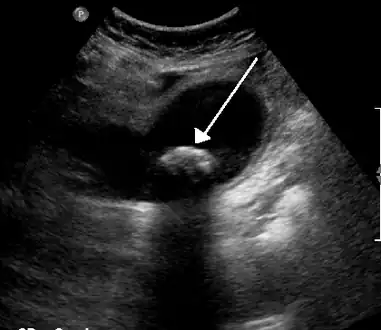

Diagnosis is typically confirmed by abdominal ultrasound. Other imaging techniques used are ERCP and MRCP. Gallstone complications may be detected on blood tests.[2]

On abdominal ultrasound, sinking gallstones usually have posterior acoustic shadowing. In floating gallstones, reverberation echoes (or comet-tail artifact) is seen instead in a clinical condition called adenomyomatosis. Another sign is wall-echo-shadow (WES) triad (or double-arc shadow) which is also characteristic of gallstones.[43]

-

A 1.9 cm gallstone impacted in the neck of the gallbladder and leading to cholecystitis as seen on ultrasound. There is 4 mm gall bladder wall thickening.